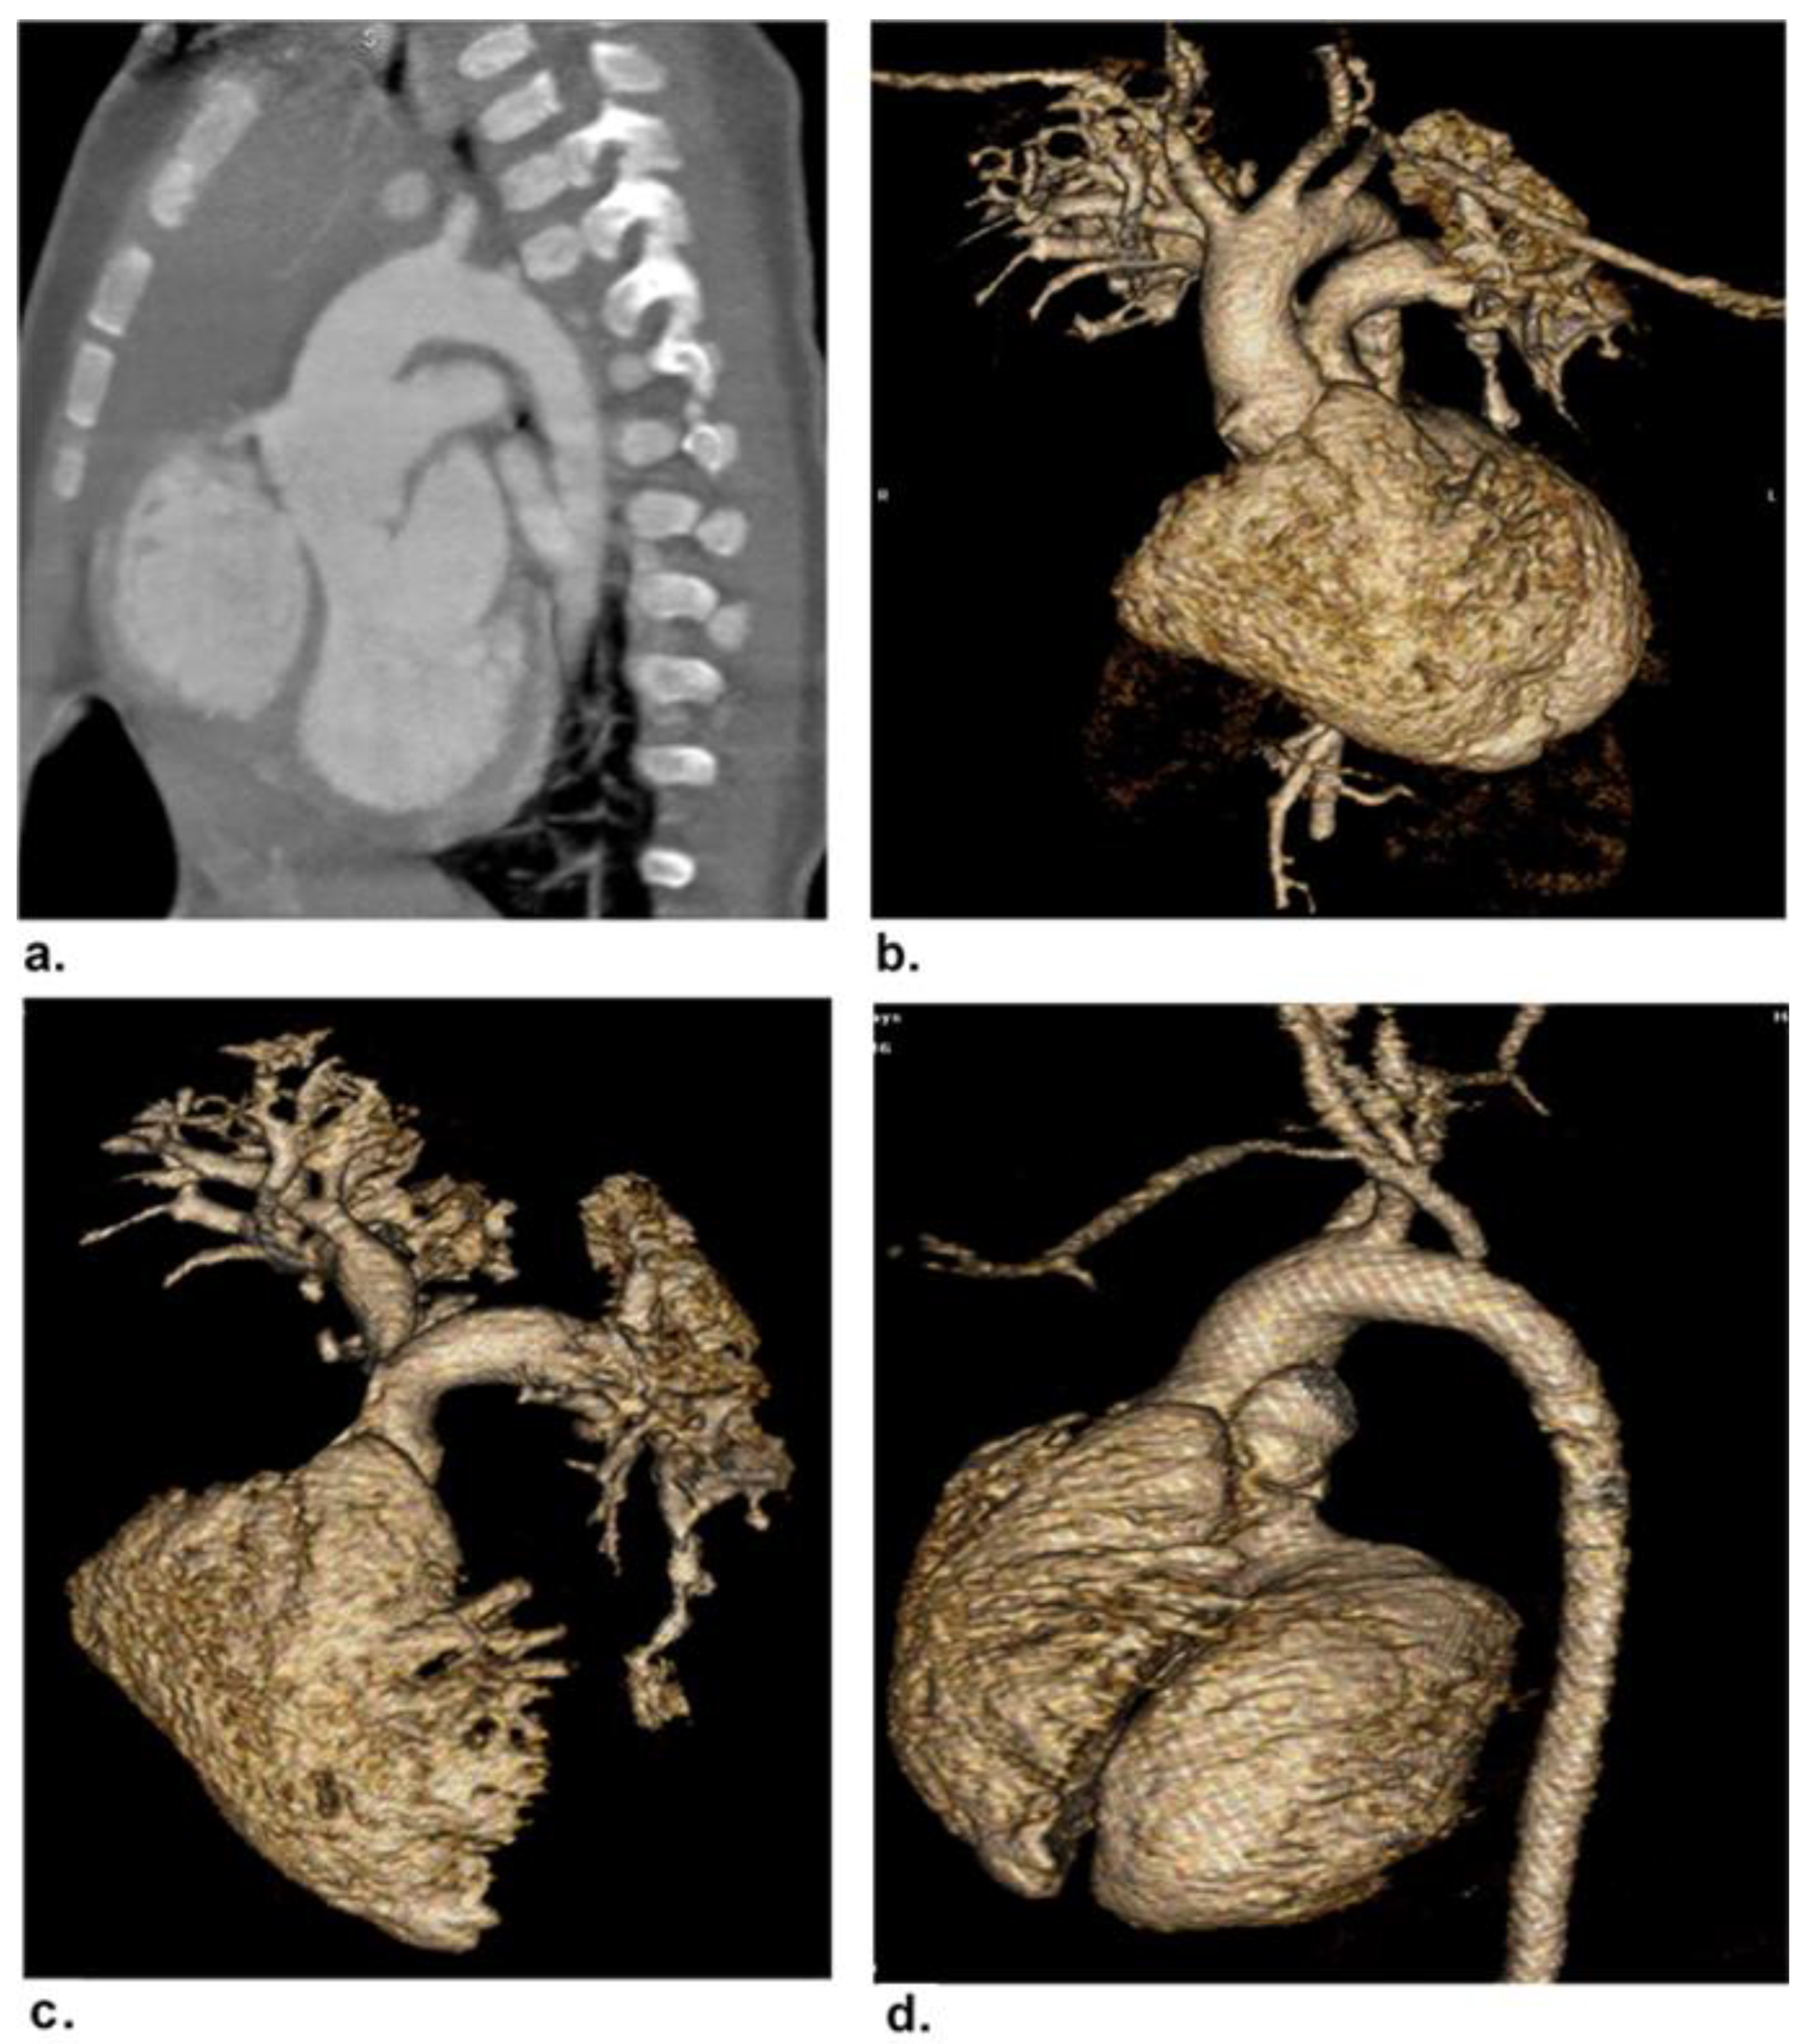

3.1. Patients and CHDs

| Intracardiac/Cardiac Malposition Ventricular septal defect Atrial septal defect Dextrocardia | 8 (11.8) 6 (8.8) 2 (2.9) |

| Conotruncal Tetralogy of Fallot Truncus arteriosus | 7 (10.3) 3 (4.4) |

| Abnormal Connection Transposition of great arteries Double outlet right ventricle | 2 (2.9) 2 (2.9) |

| Extracardiac Total anomalous pulmonary venous return Aortic coarctation Patent ductus arteriosus Double aortic arch Supravalvular aortic stenosis Pulmonary artery stenosis Pulmonary atresia Coronary artery anomalies | 4 (5.9) 6 (8.8) 10 (14.7) 1 (1.5) 3 (4.4) 7 (10.3) 3 (4.4) 4 (5.9) |